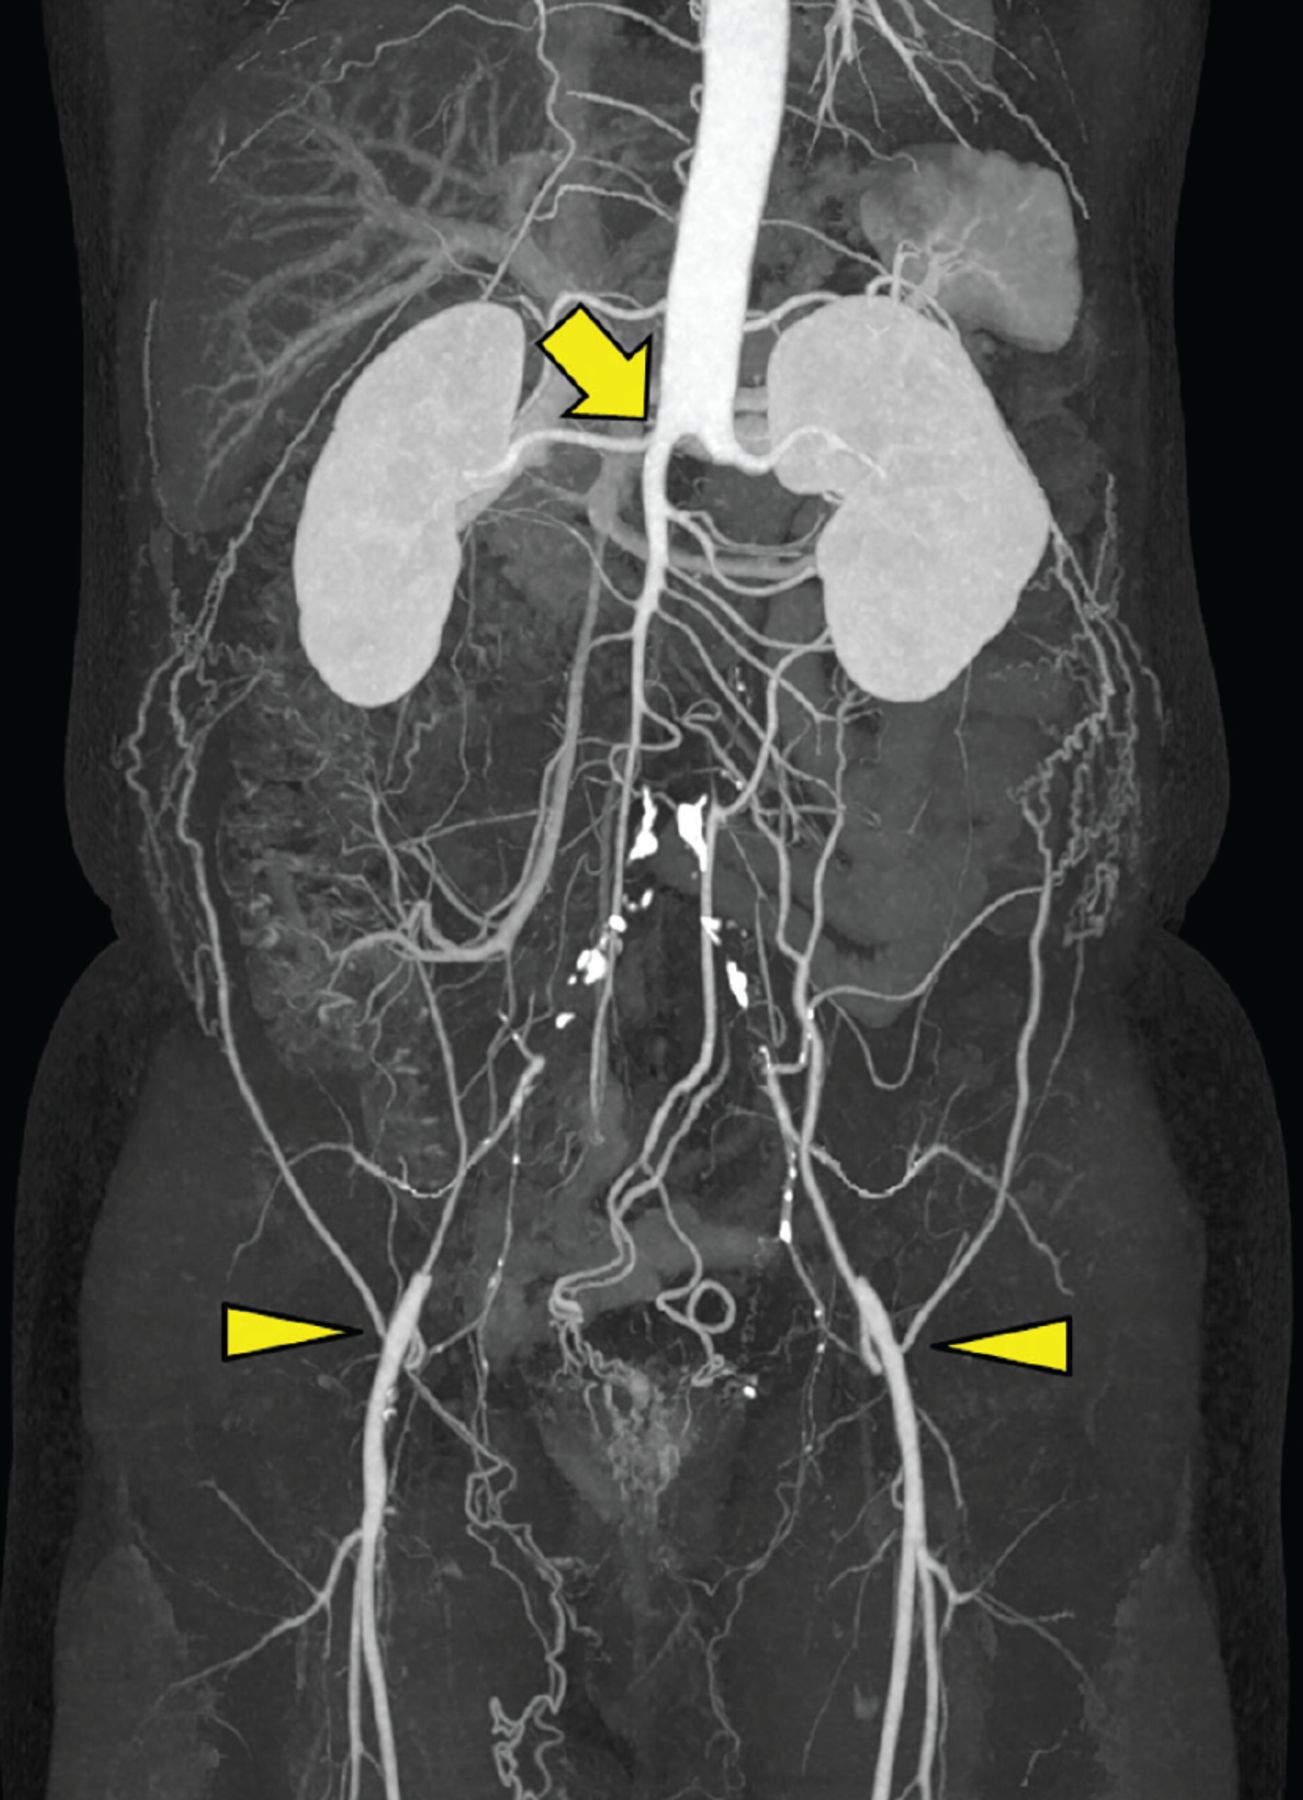

Leriche syndrome is a manifestation of occlusion of aortoiliac arteries secondary to atherosclerosis. The triad of Leriche syndrome is: - claudication - impotence - absent femoral pulses Reference: https://www.ncbi.nlm.nih.gov/books/NBK538248/ Image via: https://www.ccjm.org/content/88/9/482